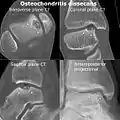

Magnetic resonance imaging (MRI) is useful for staging OCD lesions, evaluating the integrity of the joint surface, and distinguishing normal variants of bone formation from OCD by showing bone and cartilage edema in the area of the irregularity. MRI provides information regarding features of the articular cartilage and bone under the cartilage, including edema, fractures, fluid interfaces, articular surface integrity, and fragment displacement.[37][38] A low T1 and high T2 signal at the fragment interface is seen in active lesions. This indicates an unstable lesion or recent microfractures.[30] While MRI and arthroscopy have a close correlation, X-ray films tend to be less inductive of similar MRI results.[38]

Computed tomography (CT) scans and Technetium-99m bone scans are also sometimes used to monitor the progress of treatment. Unlike plain radiographs (X-rays), CT scans and MRI scans can show the exact location and extent of the lesion.[39] Technetium bone scans can detect regional blood flow and the amount of osseous uptake. Both of these seem to be closely correlated to the potential for healing in the fragment.[40][41]

CT scan and projectional radiography of a case of osteochondritis dissecans of parts of the superio-medial talus.